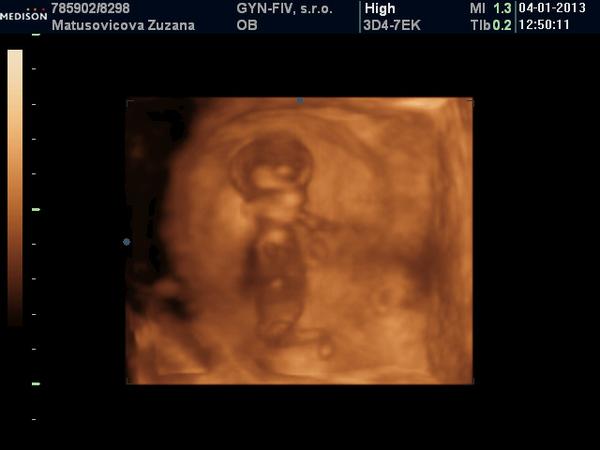

A na gynekológii všetko v poriadku. Bábo má 6,2cm. Som presne 13+0tt. NT nameral 2,2 /na 3D v piatok to bolo 1,5/. Vraj to vyzerá na chlapca, ale to mi napísal s otáznikom. Bol so mnou aj manžel aj Viki a keď vošli dnu, bábo akurát zakývalo, tak sme sa vytešovali 😉. Ale mala som vyšší tlak-140/95. Mám si dávať Magnézium ráno a večer, 3x za deň merať tlak a v piatok tam mám zavolať, že čo a ako. Ak nič, tak v pohode a ak bude vyšší, budeme to potom riešiť.